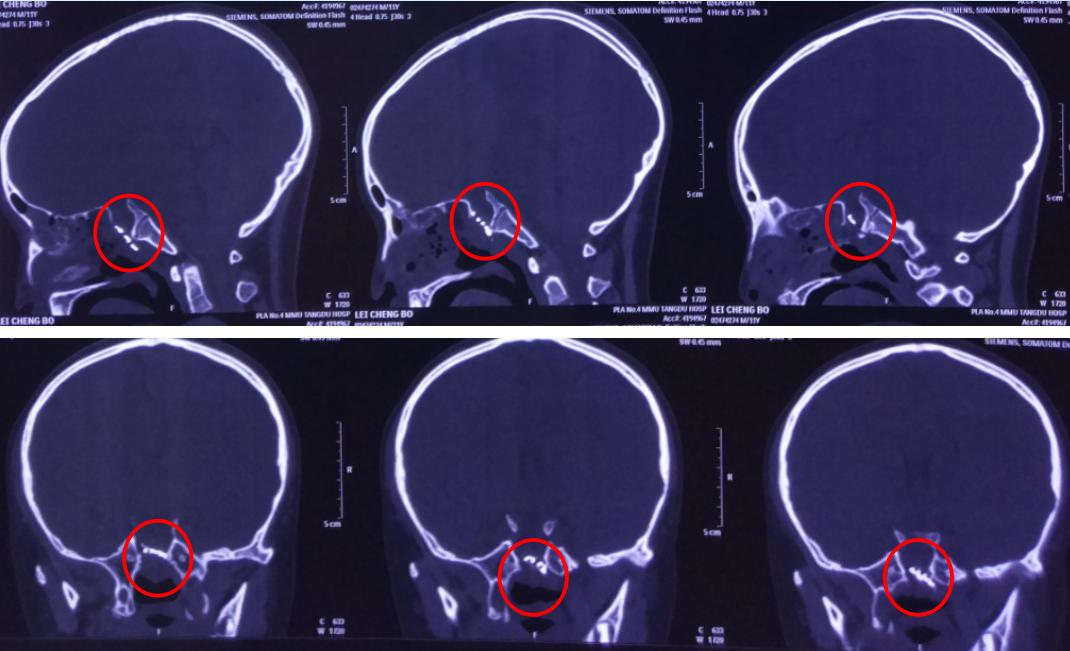

影像资料